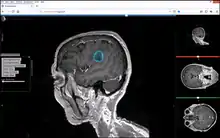

Studierfenster[1][2] is a free, non-commercial Open Science client/server-based Medical Imaging Processing (MIP) online framework. It offers capabilities, like viewing medical data (Computed Tomography (CT), Magnetic Resonance Imaging (MRI), etc.) in two-dimensional (2D) and three-dimensional space (3D) directly in a standard web browser, like Google Chrome, Mozilla Firefox, Safari or Microsoft Edge. Other functionalities are the calculation of Medical Metrics (Dice Score[3] and Hausdorff distance[4]), manual slice-by-slice outlining of structures in medical images (segmentation[5][6]), manual placing of (anatomical) landmarks in medical image data, viewing medical data in Virtual Reality (VR) and a facial reconstruction and registration of medical data for Augmented Reality (AR).[7]

Other features of Studierfenster are the automatic Cranial Implant Design with a neural network,[8][9] the inpainting of Aortic Dissections[10] with a Generative Adversarial Network(GAN)[11][12] and an automatic aortic landmark detection with Deep Learning[13] in Computed Tomography Angiography (CTA) scans.

Features